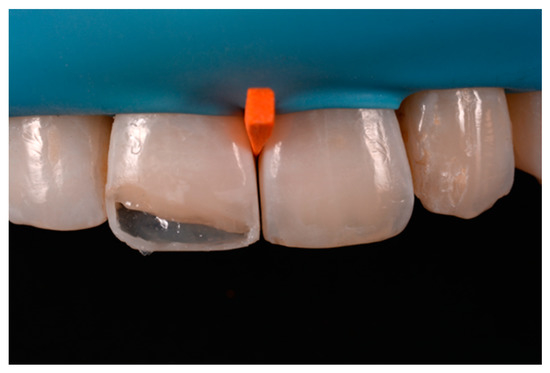

Figure 23.

Frame is completed with interproximal matrices. Reprinted from Restauri diretti nei settori anteriori, G. Paolone, S. Scolavino, © 2021, with permission from Quintessence Publishing Italy.

Figure 24.

Frame is corrected with the help of diamond burs. Reprinted from Restauri diretti nei settori anteriori, G. Paolone, S. Scolavino, © 2021, with permission from Quintessence Publishing Italy.